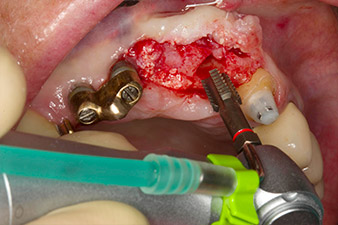

След първичното оздравяване, меките тъкани са оформени посредством базално разположения мост. Два месеца по-късно, обработваното поле е изложено на палатинална алвеоларна инцизия (Фиг 2). Размерите на алвеоларната кост са достатъчни в позиция 22. Фигури 2 и 4 показват препарацията на имплантното ложе, нарязващия винт и имплатирането, използвайки Implantmed.

пилотното изпиляване е извършено с новия Implantmed и обратен наконечник WS-56 L

Фиг. 2: Два месеца по-късно, пилотното изпиляване е извършено с новия Implantmed и обратен няконечник WS-56 L (програма P1, съотношение 1:1). Охлаждането е е осъществено чрез шлауха за физиологичен разтвор, позициониран отляво (за потребители, работещи с дясна ръка).